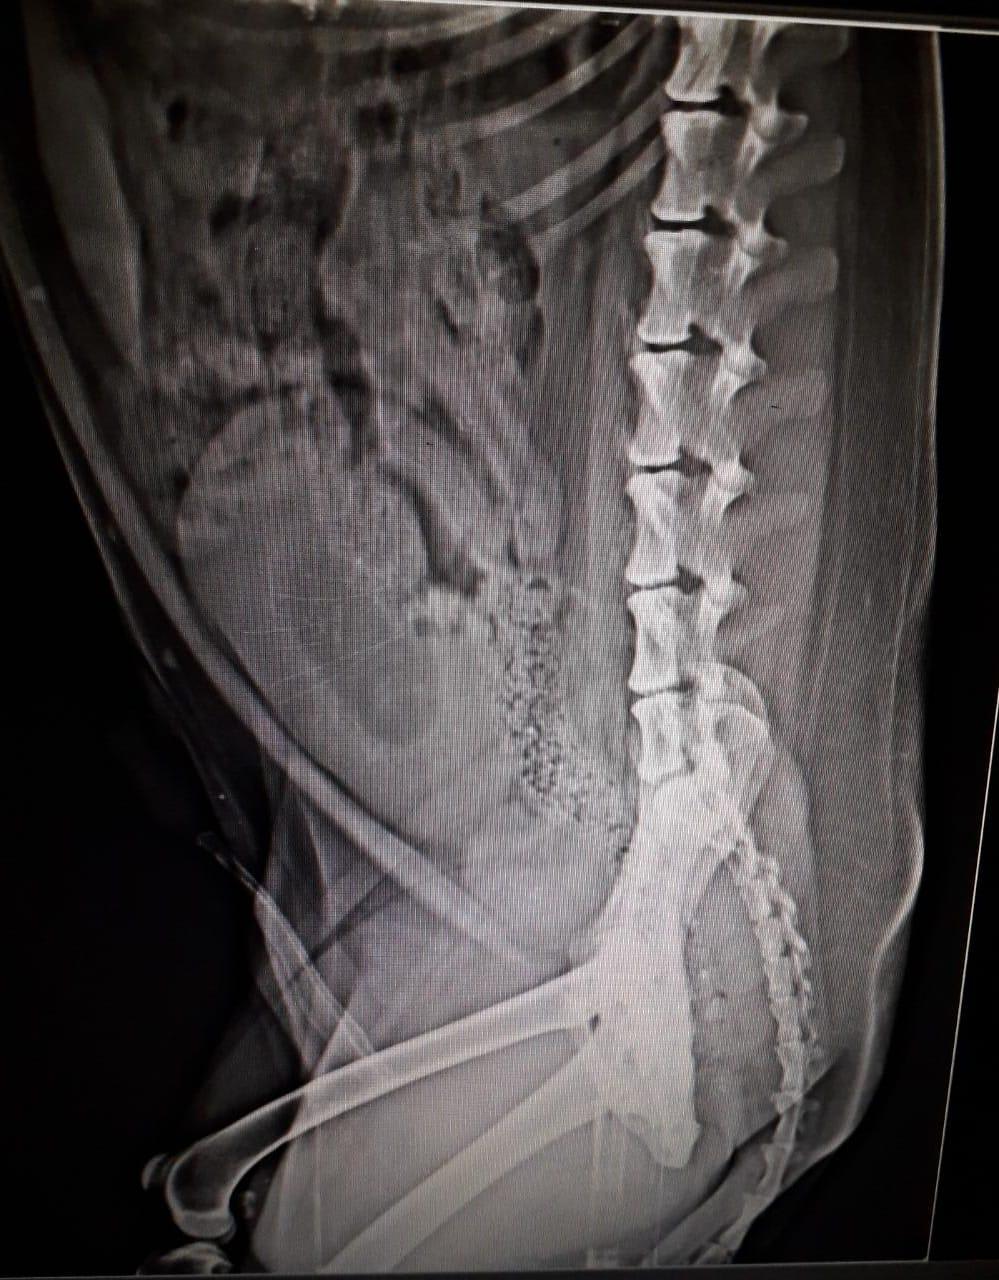

the consulting doctor is estimating tiny stones in bladder, as the urine analysis donot show the type of stone (struvite or calcium oxalate), he has prescribed alkaliser for making urine alkaline but struvite stones are dissolved in acidic urine only. please confirm if stones actually present in bladder or urinary tract and if so then best course of action. Dog is facing urinary restriction intermittently for 45 days now.

It is hard to look at x-rays through the PetCoach system, but I do not see any bladder stones. There does appear to be some gas in the bladder, which may have been inadvertently introduced through catheterization or could indicate the presence of a gas-producing bacteria. The prostate is significantly enlarged, to the point where it could constrict the urethra and cause straining to urinate. The urinalysis shows a possible infection, which could come from the bladder or prostate. I would not start urinary alkalizers without the certainty of oxalate stones. I would start antibiotics appropriate for a prostate infection and have Sheldon neutered ASAP, which can help with BPH https://www.petcoach.co/dog/condition/prostate-enlargement/